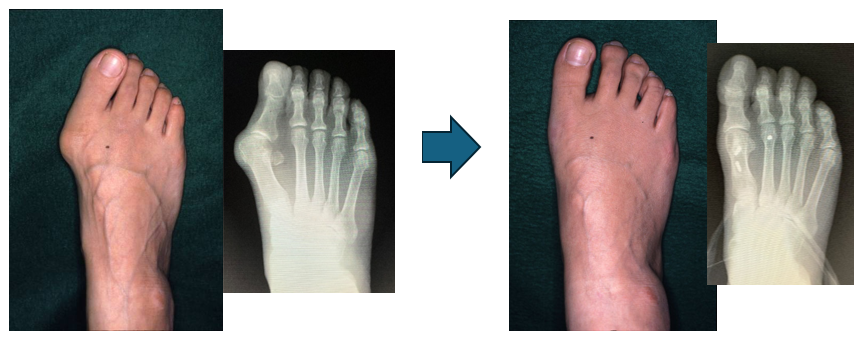

次に、より正確な評価のためにレントゲン検査を行うことが一般的です。

レントゲンでは、親指と中足骨の角度(外反母趾角)や、足全体の骨の並びを測定します。この角度が大きいほど変形が進んでいると判断され、軽度・中等度・重度と分類されます。

2. 手術療法(外科的治療)

保存療法を行っても 強い痛みが続く場合 や、靴が履けず日常生活に大きな支障がある場合 には手術が検討されます。

親指の角度を矯正する

突き出した部分を整える

歩行時の痛みや変形を改善する

手術にはいくつかの方法があり、変形の程度や年齢、生活スタイルに合わせて選択されます。

代表的なのは 骨切り術(Mitchel法、Scarf法など) や、関節の固定術(MTP関節固定術、Lapidus法など)を行う方法です。親指以外の指にも変形が波及した場合には骨長調整手術なども行われます。。